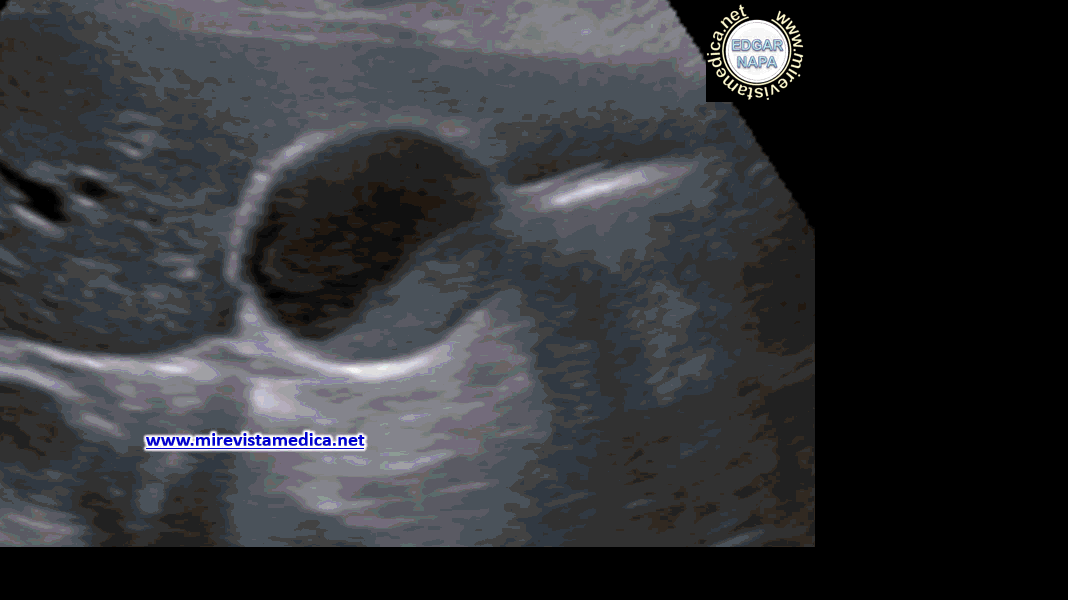

Hallazgos por ultrasonido (US_) :

- imagen hiperecogénica, movil, de márgenes circunscritos que deja sombra acústica posterior (litiasis).

- Signo de Murphy ecográfico. Pain and tenderness with transducer pressure directly over gallbladder.

- Engrosamiento de pared vesicular (se le denomina así cuando es > 3 mm). Hazy delineation of GB wall with echogenic pericholecystic fat.